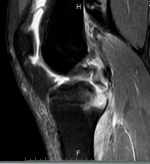

膝關(guān)節(jié)后交叉韌帶脛骨止點(diǎn)撕脫骨折 關(guān)鍵疾?。?a href="http://m.akellydesign.com/tags/so/左膝后交叉韌帶脛骨止點(diǎn)撕脫骨折-4-1.html" target="_blank">左膝后交叉韌帶脛骨止點(diǎn)撕脫骨折左膝關(guān)節(jié)半月板損傷 現(xiàn)病史【一般資料】 男性,20歲,學(xué)生 【主訴】 外傷致左膝關(guān)節(jié)疼痛、腫脹、活動受限9天 【現(xiàn)病史】 9天前外傷致左膝關(guān)節(jié)疼痛、腫脹、活動受限,站立、行走困難,就診于當(dāng)?shù)蒯t(yī)院,給予局部理療等對癥治療,治療后疼痛稍緩解,腫脹稍減輕。為進(jìn)一步治療,今至我院求治。門診經(jīng)檢查后以“左膝后交叉韌帶脛骨止點(diǎn)撕脫骨折”為診斷收入我科。發(fā)病以來,神志清楚,精神尚可,無惡寒發(fā)熱,飲食、大小便正常,睡眠可,體重?zé)o明顯變化。 【既往史】 平素體健,無肝炎、結(jié)核等傳染病史,無其它外傷、手術(shù)史,無輸血、中毒史,無明確藥物過...

膝關(guān)節(jié)內(nèi)側(cè)半月板撕裂并囊腫一例 現(xiàn)病史【一般資料】男性,36歲,公務(wù)員【主訴】扭傷后左膝關(guān)節(jié)腫脹、疼痛,活動受限7天【現(xiàn)病史】1天前在打籃球時不慎扭傷右膝關(guān)節(jié)后出現(xiàn)右膝關(guān)節(jié)疼痛腫脹活動受限,站立、行走困難,后于當(dāng)?shù)蒯t(yī)院行MRI提示:右膝前交叉韌帶撕裂。為進(jìn)一步治療,今至我院求治。門診經(jīng)體格檢查后以“右膝前交叉韌帶撕裂”為診斷收入我科。發(fā)病以來,神志清楚,精神尚可,無惡寒發(fā)熱,飲食、大小便正常,睡眠可,體重?zé)o明顯變化。【既往史】12年前因右膝半月板損傷行右膝半月板部分切除術(shù)。否認(rèn)“高血壓、冠心病、糖尿病”病史,否認(rèn)肝炎、結(jié)核等傳染...